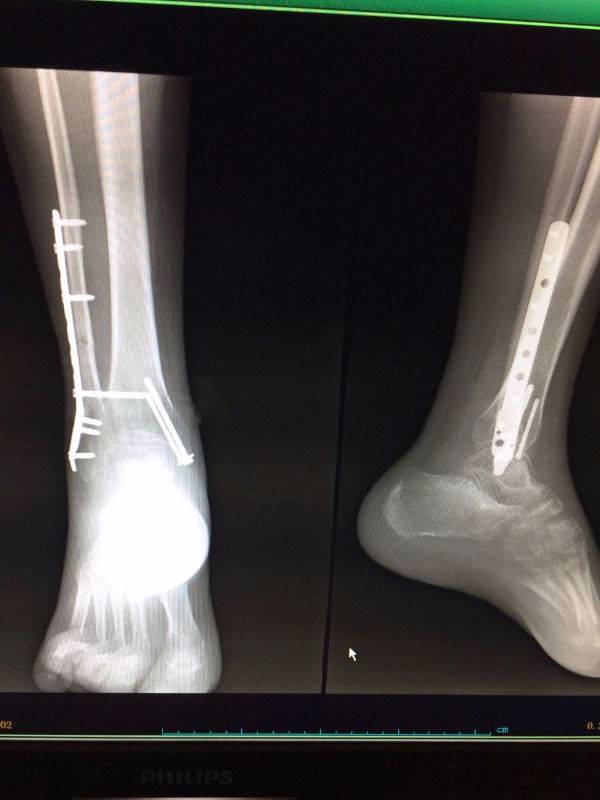

手术非常好,顺便请教一下。患者.男,25岁,右腓骨下段及内踝骨折,切开复位内固定术后120天,外踝部钢板外露,半月前行扩创缝合,目前仍未完全愈合,伴少量渗出,踝关节功能僵硬。请教治疗方案。谢谢

mmexport1496478281296.jpg

mmexport1496478334909.jpg

mmexport1496478329835.jpg

mmexport1496478319278.jpg